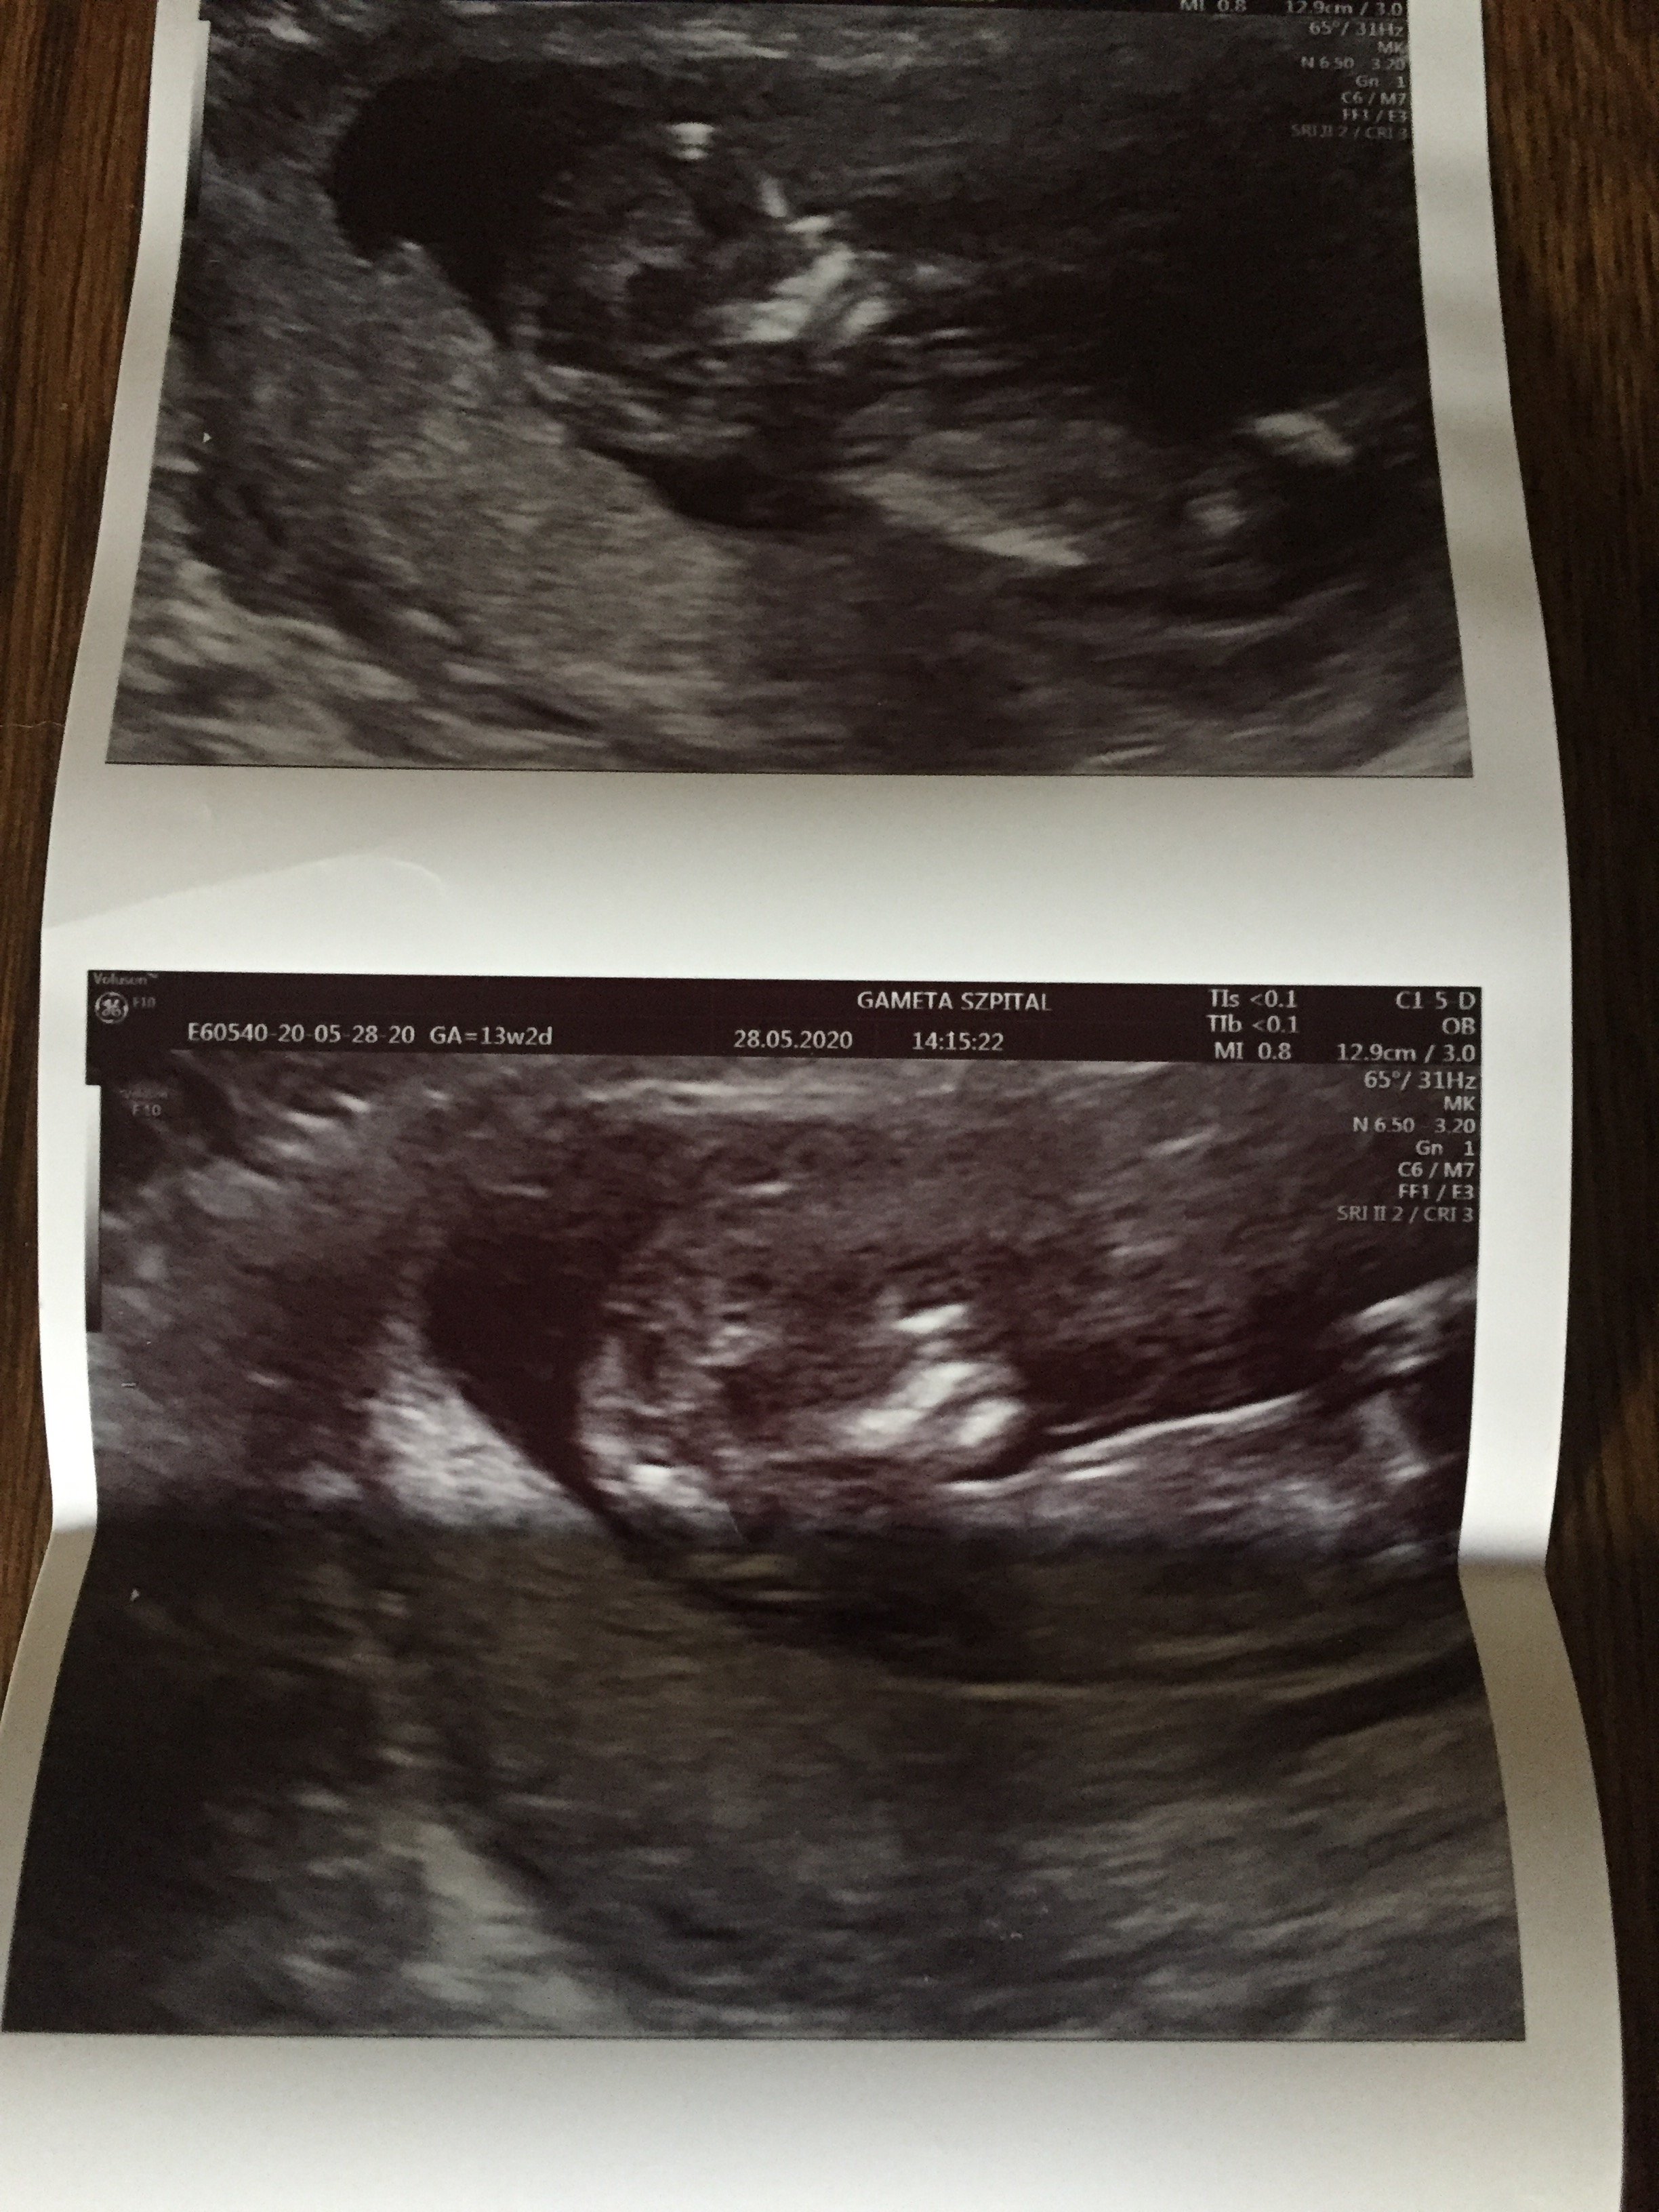

Dziś miałam prenatalne i w usg wszystko dobrze,Na razie mam wynik tylko z samego usg i jest 1:4xxx, z pappa bede miala wynik w przyszłym tygodniu. Ciekawe jak sie zmieni.

A jakie miałaś CRL do tego NT?Dziś miałam prenatalne i w usg wszystko dobrze,

Nt: 1,3mm

Kość nosowa widoczna

przepływy też ok

A ryzyko 21 podstawowe 1:533

Skorygowane1:762

Pappa z krwi wyszła mi trochę nisko

I tak się trochę martwię....

Pięknie, serdeczne gratulacjeNo i ja się w końcu pochwale moja kruszynka ❤ Mamy prawie 7 cm (6,8) dziś 13 równy tydzień wiec jutro wkraczamy w 14 wowwszystko prawidłowo na usg prenatalnym żadnych uwag zdrowa dzidzia. Najważniejsze, ze krwiak się całkowicie wchłonął juuupi nie ma po nim śladu

70,0mmA jakie miałaś CRL do tego NT?

Ja mialam NT 1,82 dla długości jakos 69mm